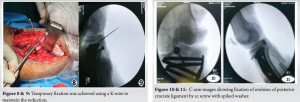

We planned to manage both fractures in a two-stage surgery. The selected approach involved open reduction internal fixation of fracture proximal tibia by LCP followed by open reduction and internal fixation of PCL avulsion using cannulated cancellous screws, supplemented by the innovative application of a spiked washer for enhanced stability. Post-operative X-ray after open reduction and internal fixation of the proximal tibial fracture with an LCP (R) (Fig. 5). The implant is appropriately aligned, with satisfactory reduction and fixation of the fracture fragments, ensuring stability for healing. The interval between the two surgeries was 10 days, allowing time for the skin incision to heal and the soft-tissue swelling to subside. Following the acquisition of informed consent, the patient was planned for ORIF using cannulated cancellous screws and spiked washer, employing the modified posterior approach as detailed by Burks and Schaffer [6]. The patient underwent surgery under spinal anesthesia. He was placed in a prone position on a radiolucent operating table, ensuring adequate padding for pressure points. The lower extremity was positioned with a 30° flexion at the knee joint, supported by a bolster at the ankle, and a pneumatic tourniquet was applied to the patient. An inverted “L”-shaped incision was performed, starting from the medial aspect of the gastrocnemius and curving along the joint’s flexor crease toward the lateral side (Fig. 6).

The fascia was cut following the path of the skin incision. The capsule was reached through the space between the semimembranosus and gastrocnemius (Fig. 7). A lengthwise incision was made, exposing the joint at the location of the avulsed fragment. The avulsed fragment was carefully refreshed and realigned. A slight flexion of the knee joint aided in the reduction process. Temporary fixation was achieved using a K-wire to maintain the reduction (Fig. 8 and 9).

The insertion site for the cannulated cancellous (CC) screw was located and subsequently drilled with a cannulated drill bit. Ultimately, the avulsed fragment was secured by employing a 4 mm cannulated cancellous screw along with a spiked washer, which was screwed in place over the guide wire. The K-wire used for temporary fixation was then removed (Fig. 10-12).